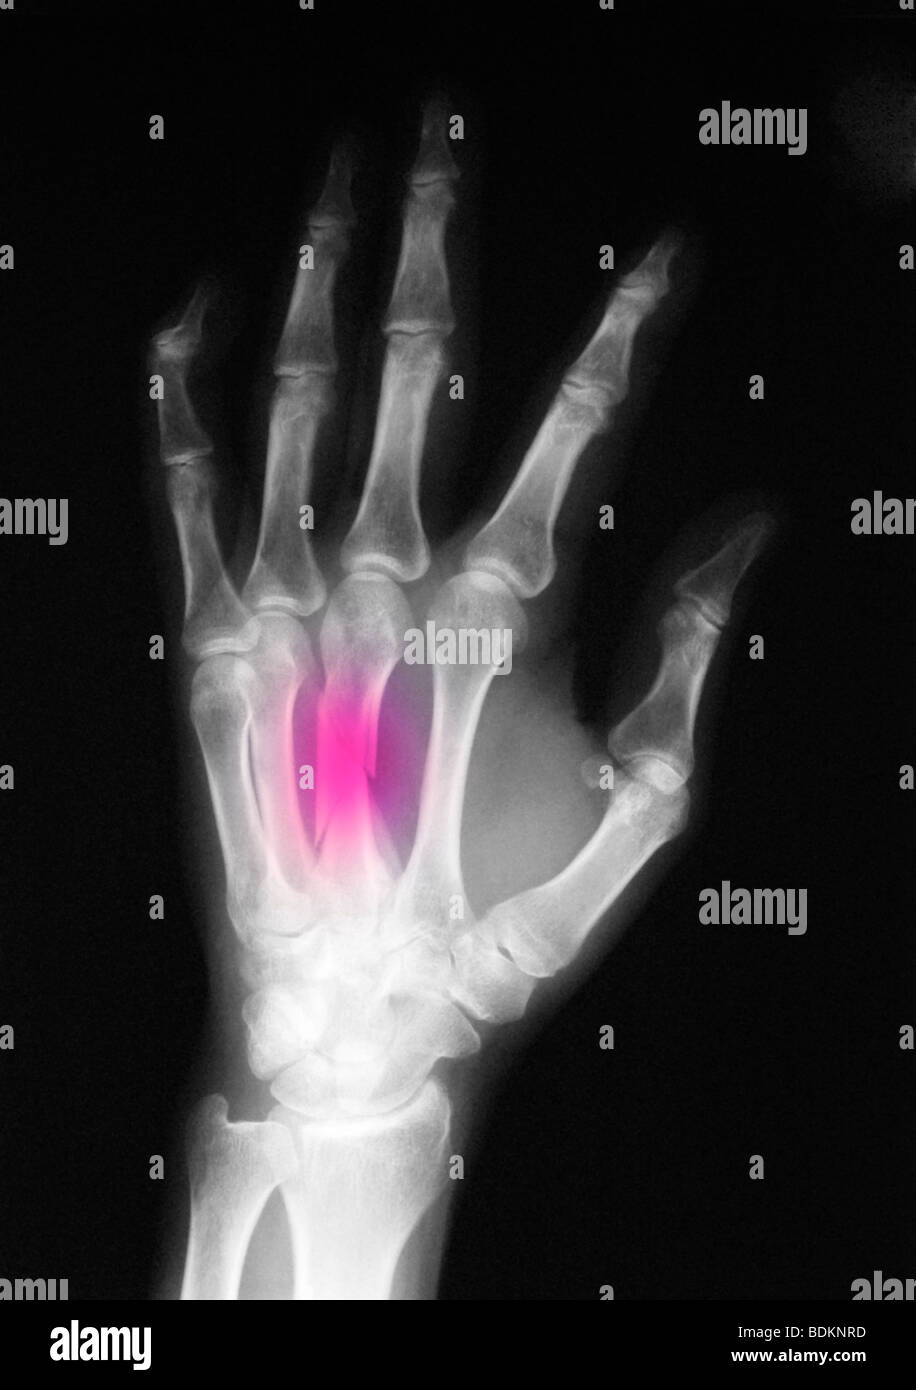

Hand Xray Showing Spiral Fractured Third Metacarpal Bone Stock Photo Metacarpal Fracture X Ray treatment & management. They usually occur due to a blunt force. the second metacarpal head (ray of index finger) is most commonly involved, and the first metacarpal head. This article reviews metacarpal fractures and dislocations in the hand. metacarpal fractures are the most common hand injury and are divided into fractures of the head, neck, or shaft.. Metacarpal Fracture X Ray.